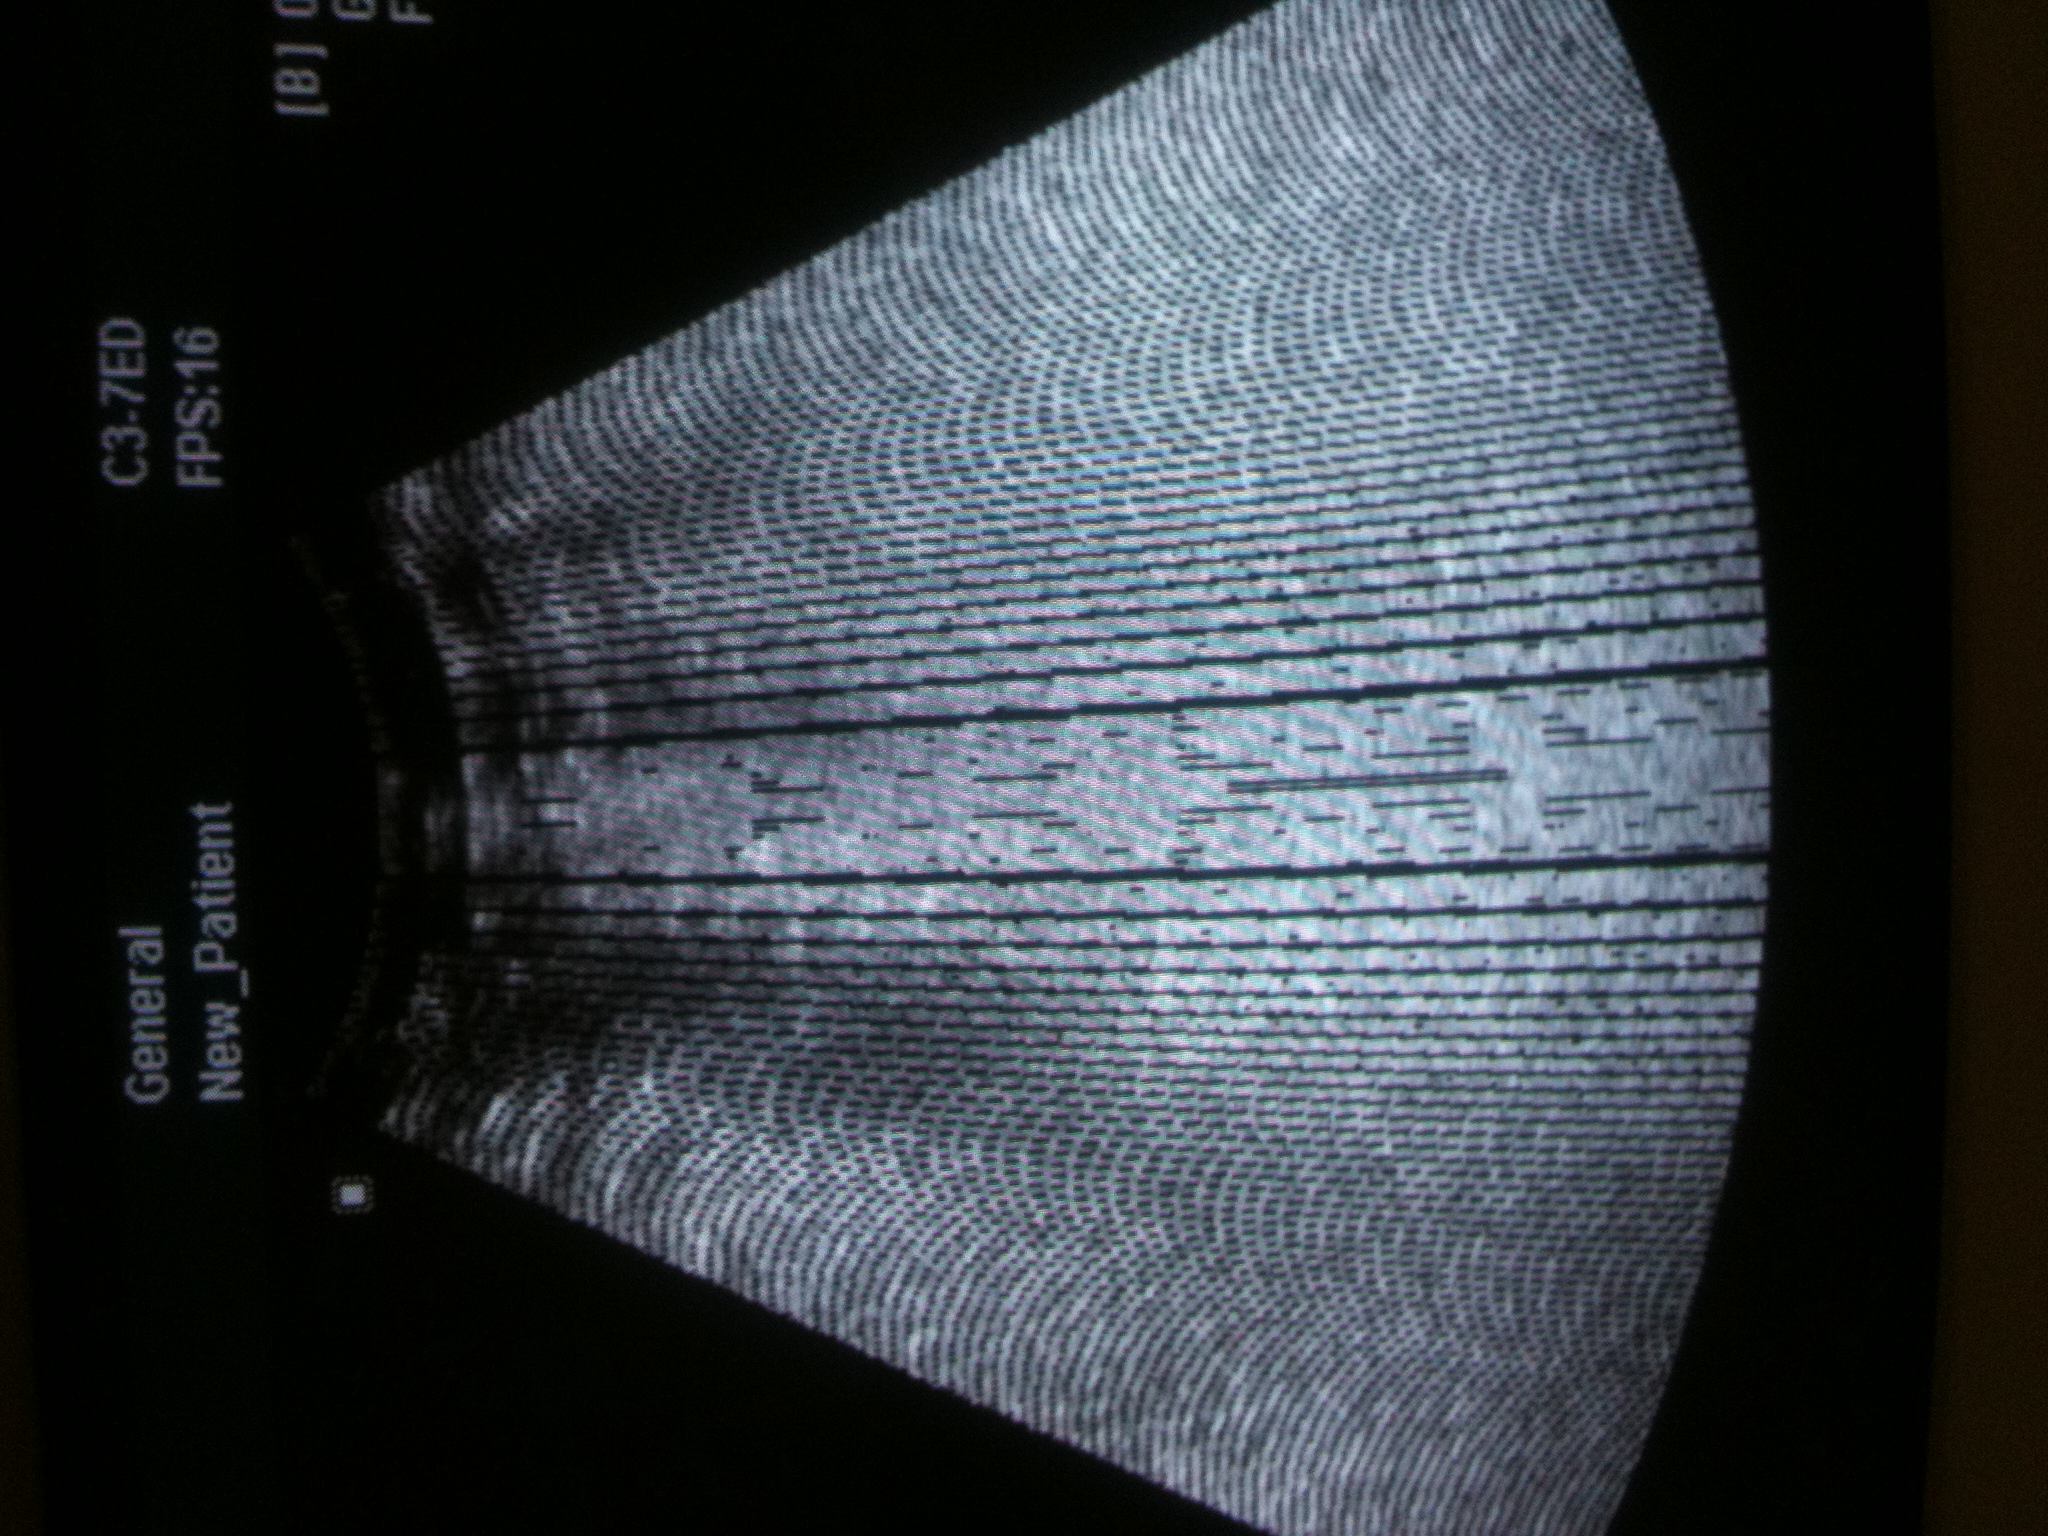

求助各位高手现有麦迪逊6000c开机后故障如下图,开机半小时后关机在开机恢复正常。考虑电源问题打开电源后发现滤波电容有点鼓更换后,开机没有好转反而加重先考虑是不是更换的滤波电容不合格。还请各位多提意见谢谢。

除了高频探头没有干扰外,腹部和腔内都有干扰。

这个是DSC问题